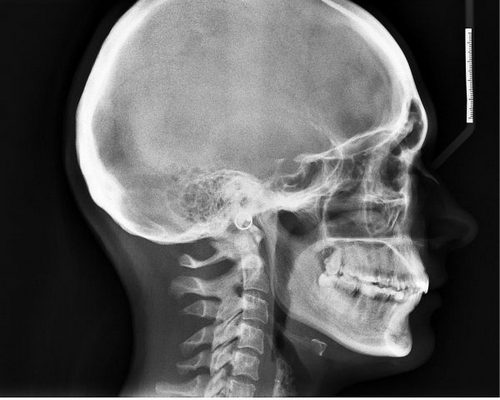

Безусловно, перед началом лечения крайне важно пройти профессиональную диагностику. С ее помощью удастся точно выяснить, с чем именно приходится иметь дело. Не стоит самостоятельно принимать медикаменты, потому как они могут оказаться неэффективны. Курс лечения должен быть назначен в зависимости от ситуации. Например, врач может направить пациента на МРТ и КТ. Эти исследования являются достаточно информативными и позволяют выявить многие патологии мозга. Также нередко назначают рентген, он особенно полезен в случае травм головы.

- компьютерная ренгеновская томография: наиболее точный метод диагностирования патологий органов и систем в человеческом теле. Сегодня КТ часто применяют для установления каких-либо отклонений в работе головного мозга. Методика, во-первых, безопасна, а во-вторых, очень точна. С ее помощью обнаруживаются опухоли и другие новообразования в черепе, устанавливаются любые проблемы с кровообращением в церебральных сосудах или угнетением ЦНС. После процедуры врач получает четкое изображение костей, мозговых оболочек и артерий.

Для проведения КТ требуется специальный аппаратам – томограф. Процедура проходит либо с введением контрастного вещества, либо без него, анестезия при этом не требуется. Пациент находится в положении лежа на спине или на боку. Человек все время обследования должен лежать неподвижно, нельзя садиться или подниматься. Именно по этой причине КТ не всегда рекомендуют для маленьких детей или людей с психическими отклонениями. Таким категориям КТ делают под наркозом;

- магнитно-резонансная томография: альтернатива КТ, когда рентген противопоказан. Наиболее часто к МРТ прибегают, чтобы установить локализация и размеры новообразований в черепе, проверить состояние мозга до и после операции, понять, отчего у человека возникают приступы головной боли, обмороки. МРТ фактически дает врачу полное представление о состоянии всех мозговых структур;